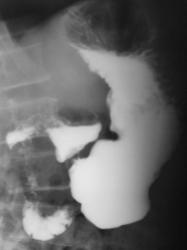

Пациент, который длительное время находился на диспансерном учете, как "язвенный больной", в последние годы не обследовался. Отмечает, что болей не ощущает, но очень резко похудел за последние два года.

нехорошая язва, уже может быть и инфильтративно-язвенные рак, биопсию надо делать

Ригидность контуров всего тела желудка, центральный дефект наполнения в теле, изьязвление по малой кривизне, кисетообразная деформация всего желудка - убедительные признаки обширного опухолевого поражения.